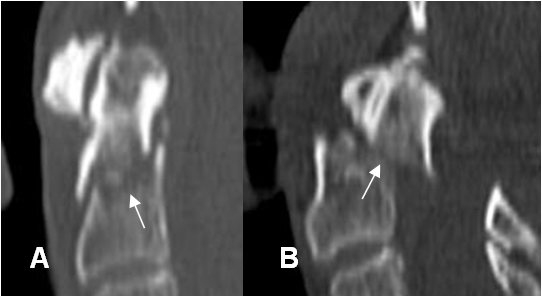

Fig 198 A. Fractura de odontoides tipo I.

A: TAC axial y B: TAC reconstrucción lateral. Imagen radiolúcida y en sentido oblicuo, en la parte superior de la odontoides,que corresponde a fractura no desplazada.(Flechas).

Fig 198 B. Fractura de odontoides tipo II.

A y B: TAC axial. Fracturas en sentido oblicuo, sobre la parte media de la odontoides. En A no desplazada y en B desplazada y con subluxación C1-C2.

Fig 199. Fractura de odontoides tipo III.

A: Rx AP. No se encuentran alteraciones. B y C: TAC axial y D: TAC reconstrucción sagital. Fractura en sentido oblicuo, sobre el cuerpo de C2, por fractura de la odontoides tipo III. (Flechas).